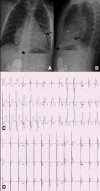

Atrioventricular block is classified as congenital if diagnosed in utero, at birth, or within the first month of life. The pathophysiological process is believed to be due to immune-mediated injury of the conduction system, which occurs as a result of transplacental passage of maternal anti-SSA/Ro-SSB/La antibodies. Childhood atrioventricular block is therefore diagnosed between the first month and the 18th year of life. Genetic variants in multiple genes have been described to date in the pathogenesis of inherited progressive cardiac conduction disorders. Indications and techniques of cardiac pacing have also evolved to allow safe permanent cardiac pacing in almost all patients, including those with structural heart abnormalities.

What is known: • Prevalence of congenital heart block of 1 per 15,000 to 20,000 live births. AV block is defined as congenital if diagnosed in utero, at birth, or within the first month of life, whereas childhood AV block is diagnosed between the first month and the 18th year of life. As a result of several different etiologies, congenital and childhood atrioventricular block may occur in an entirely structurally normal heart or in association with concomitant congenital heart disease. Cardiac pacing is indicated in symptomatic patients and has several prophylactic indications in asymptomatic patients to prevent sudden death. • Autoimmune, congenital AV block is associated with a high neonatal mortality rate and development of dilated cardiomyopathy in 5 to 30 % cases. What is New: • Several genes including SCN5A have been implicated in autosomal dominant forms of familial progressive cardiac conduction disorders. • Leadless pacemaker technology and gene therapy for biological pacing are promising research fields. In utero percutaneous pacing appears to be at high risk and needs further development before it can be adopted into routine clinical practice. Cardiac resynchronization therapy is of proven value in case of pacing-induced cardiomyopathy.